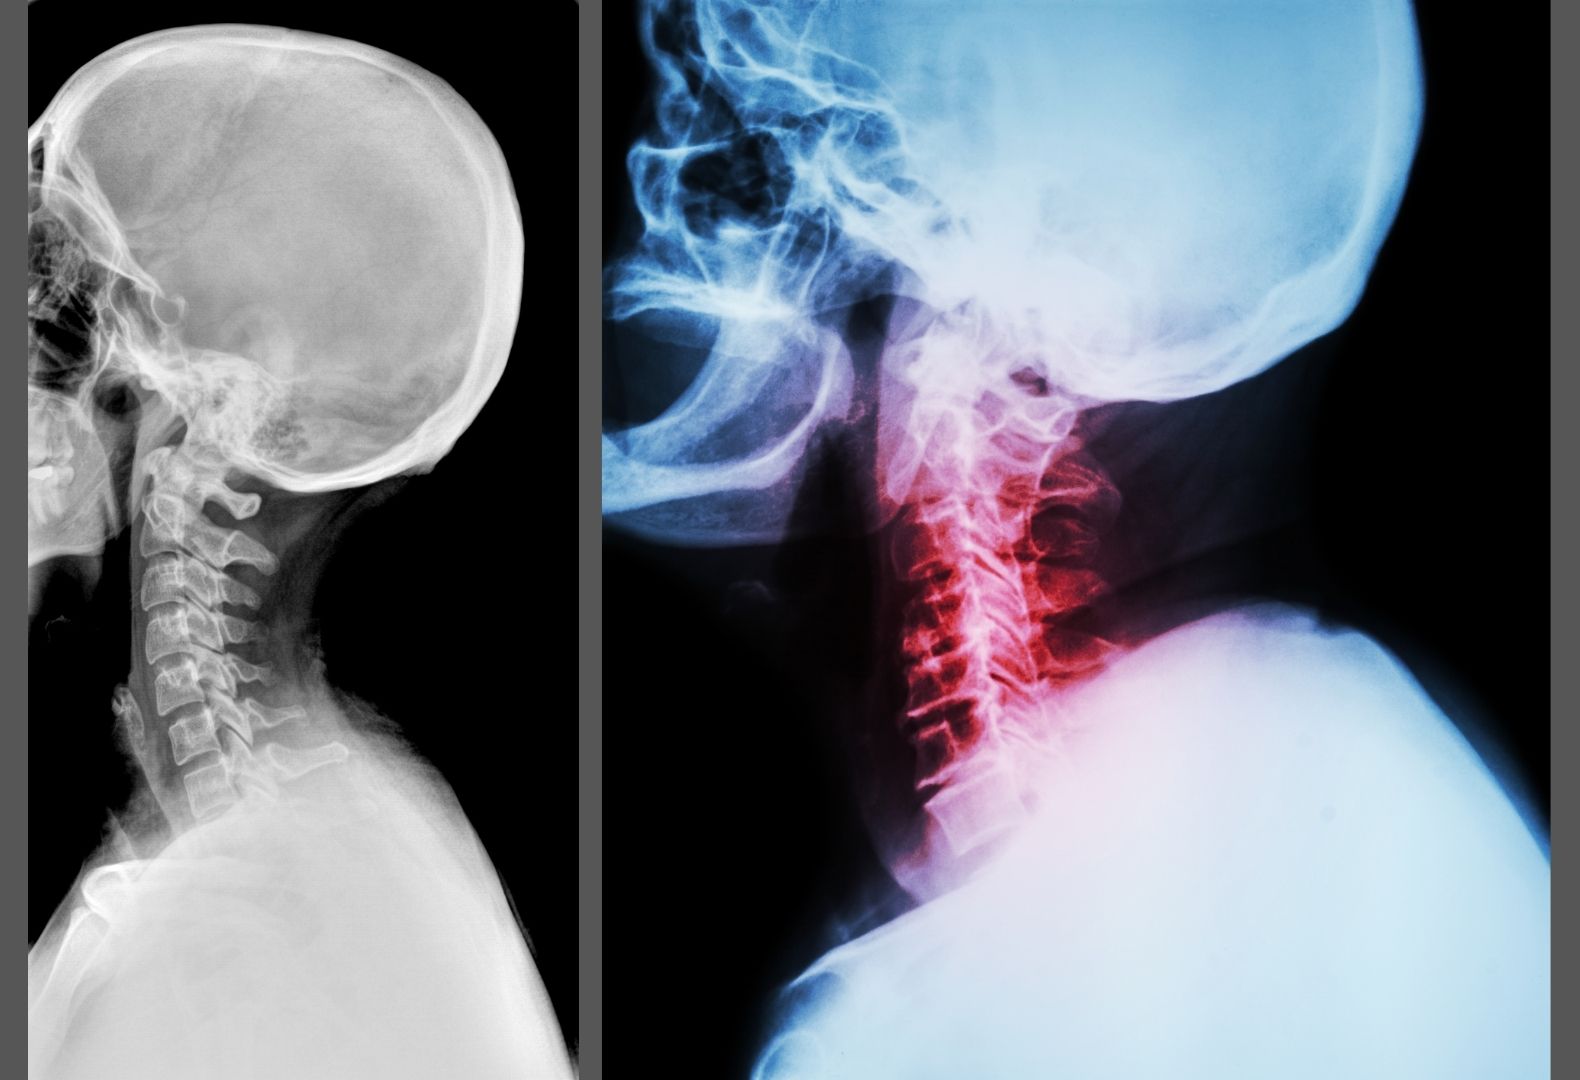

What Causes No Curve In Neck . Military neck is an abnormal curve of the cervical spine that causes you to look like you’re “standing at attention.” the condition, called cervical kyphosis, doesn’t have. A crooked neck could mean that your cervical vertebrae have shifted out of alignment. Once that happens, symptoms of cervical kyphosis vary and can range from mild. If you have military neck, also called cervical kyphosis, your neck has lost some of its normal curvature. An overview of cervical degenerative kyphosis. In individuals with straight neck syndrome, the neck appears straight when viewed from the side, instead of having the normal gentle curve. The cervical spine in its normal relaxed position aligns in a curved orientation called a. In this post, we’ll discuss everything about. Cervical kyphosis, or military neck, occurs when your cervical spine is straight or curves toward your front instead of its natural curve to your.

In this post, we’ll discuss everything about. If you have military neck, also called cervical kyphosis, your neck has lost some of its normal curvature. In individuals with straight neck syndrome, the neck appears straight when viewed from the side, instead of having the normal gentle curve. Cervical kyphosis, or military neck, occurs when your cervical spine is straight or curves toward your front instead of its natural curve to your. A crooked neck could mean that your cervical vertebrae have shifted out of alignment. An overview of cervical degenerative kyphosis. Military neck is an abnormal curve of the cervical spine that causes you to look like you’re “standing at attention.” the condition, called cervical kyphosis, doesn’t have. The cervical spine in its normal relaxed position aligns in a curved orientation called a. Once that happens, symptoms of cervical kyphosis vary and can range from mild.